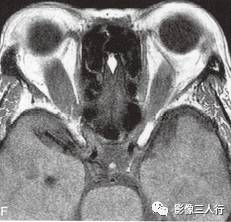

A~C.抑脂T2WI横断面;D~F.T1WI横断面;G~H.T1WI冠状面;I.抑脂T2WI冠状面

横断面显示双侧眼球明显突出,双侧眼球角膜至双侧颧突连线的垂直距离分别为:右侧2.2cm、左侧2.3cm。双侧眼外肌明显增粗,以双侧内、外、上、下直肌明显,短径均可达7mm,且以肌腹增粗明显呈梭形,T1WI等信号(图D~F,图G~H),抑脂T2WI呈明显高信号(图A~C,图I)。双侧眼眶内及球后脂肪增多,双侧眼球内侧至眼眶内侧壁的脂肪厚度增宽。双侧视神经形态及走行正常,双侧眼球晶体、玻璃体形态及信号正常。

影像学检查可帮助该病的诊断与鉴别诊断。CT表现为眼外肌增粗,主要为肌腹增粗,附着于眼球壁上的肌腱不增粗,少数也可同时累及眼外肌肌腹和肌腱。最常累及下直肌,其次为内直肌、上直肌和上提肌,偶尔累及外直肌。MRI表现为受累的眼外肌T1WI低信号,T2WI高信号,压脂T2WI为高信号;晚期眼外肌已纤维化,在T1WI和T2WI均呈低信号。增强扫描急性期时增粗的眼外肌有轻至中度强化,晚期眼外肌纤维化时则无强化。眶内脂肪体积增多表现为球周脂肪尤其是眶前部脂肪的增多。本例影像征象较典型。